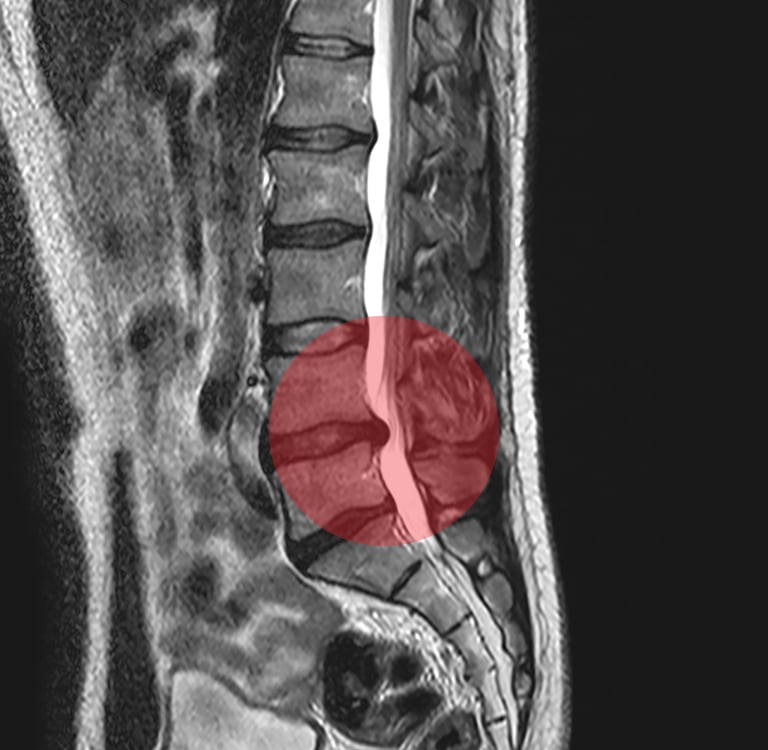

No início do tratamento, o objetivo principal é aliviar a dor por meio de terapias manuais, como Osteopatia, Quiropraxia, e técnicas de Mulligan e Maitland, além de exercícios específicos para descompressão e redução da dor neural. Estas abordagens proporcionam conforto e bem-estar, preparando o paciente para a fase seguinte do tratamento.

Durante a fase intermediária da reabilitação, aplicam-se exercícios terapêuticos ativos voltados para a coluna, além de técnicas específicas para estabilização ou mobilidade. O propósito é restaurar a função, aprimorar a mobilidade e resistência, aliviar a dor e preparar o paciente para a etapa subsequente de fortalecimento.

Na etapa final do tratamento, o foco é o fortalecimento muscular e a recuperação das funções da coluna. São indicados exercícios específicos para dar estabilidade e suporte vertebral. Com um programa direcionado, é possível reabilitar, prevenir novas lesões e manter a saúde da coluna.